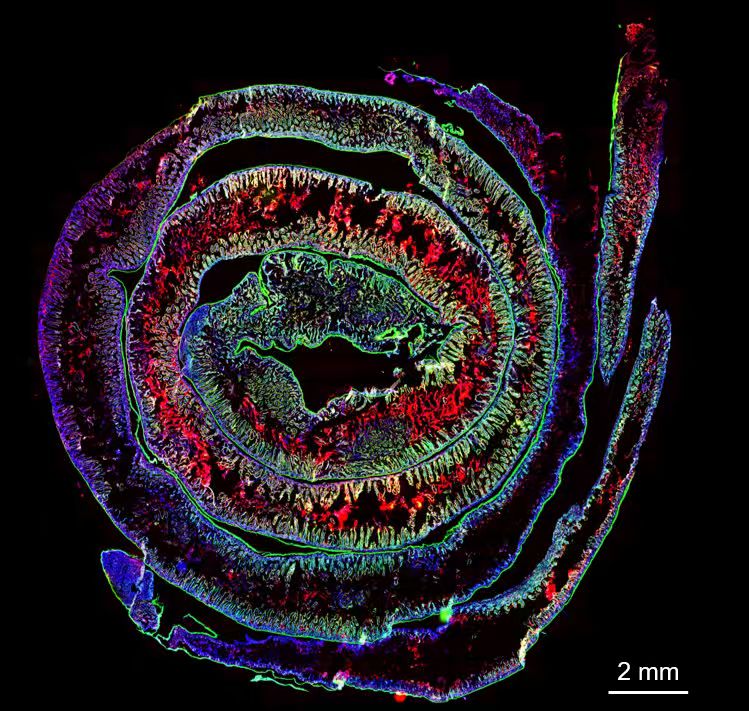

2. In Vivo Fate of Drug Delivery Systems

We systematically investigate the in vivo behavior and fate of drug delivery systems using advanced imaging and analytical tools, including intravital fluorescence microscopy, transmission electron microscopy, and synchrotron radiation-based imaging. Our studies focus on how delivery systems interact with physiological and immune barriers, such as the mononuclear phagocyte system (especially in the liver and spleen), vascular endothelium, and immune cell subsets. We analyze circulation kinetics, biodistribution profiles, cellular uptake mechanisms, and clearance pathways to elucidate the principles that govern delivery efficiency and target-site accumulation. These mechanistic insights guide the rational optimization of carrier design to improve therapeutic precision and minimize systemic toxicity.